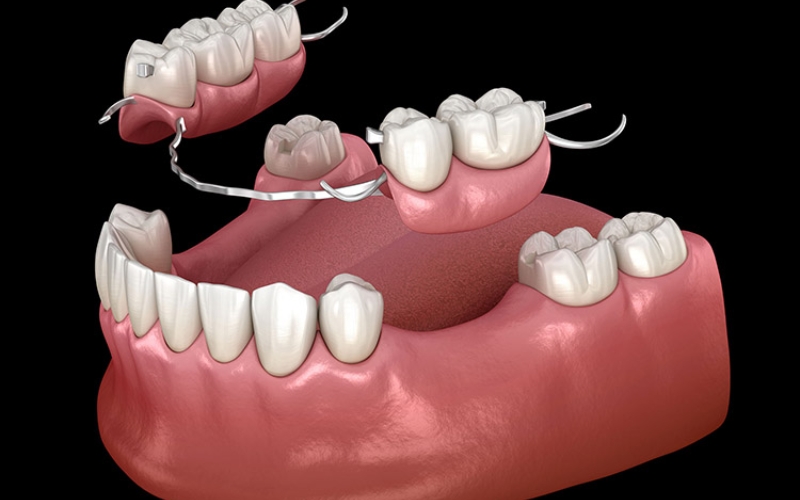

Hàm giả tháo lắp:

- Hàm giả tháo lắp là phương pháp được nhiều người cao tuổi lựa chọn.

- Tuy nhiên phương pháp này chỉ có tính thẩm mỹ tạm thời, do hàm không đủ lực nên sẽ làm cản trợ khả năng ăn nhai.